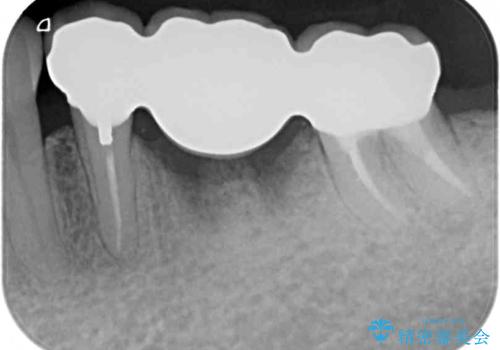

抜かずに保存した奥歯が痛くて臭う セラミックブリッジによる欠損補綴治療

前後の歯も大きな銀歯が装着されていたので、抜歯後に治癒を待って、フルジルコニアブリッジにて補綴することとしました。

抜歯をしたことで、ずっと気になっていた異臭から解放されました。

前後の歯はいずれも神経が取り除かれている歯であったので、ブリッジ治療では負担が大きくなることが懸念されました。咬合力はさほど強くない咬み合わせであったので、インプラントではなく、ブリッジ治療を選択されました。